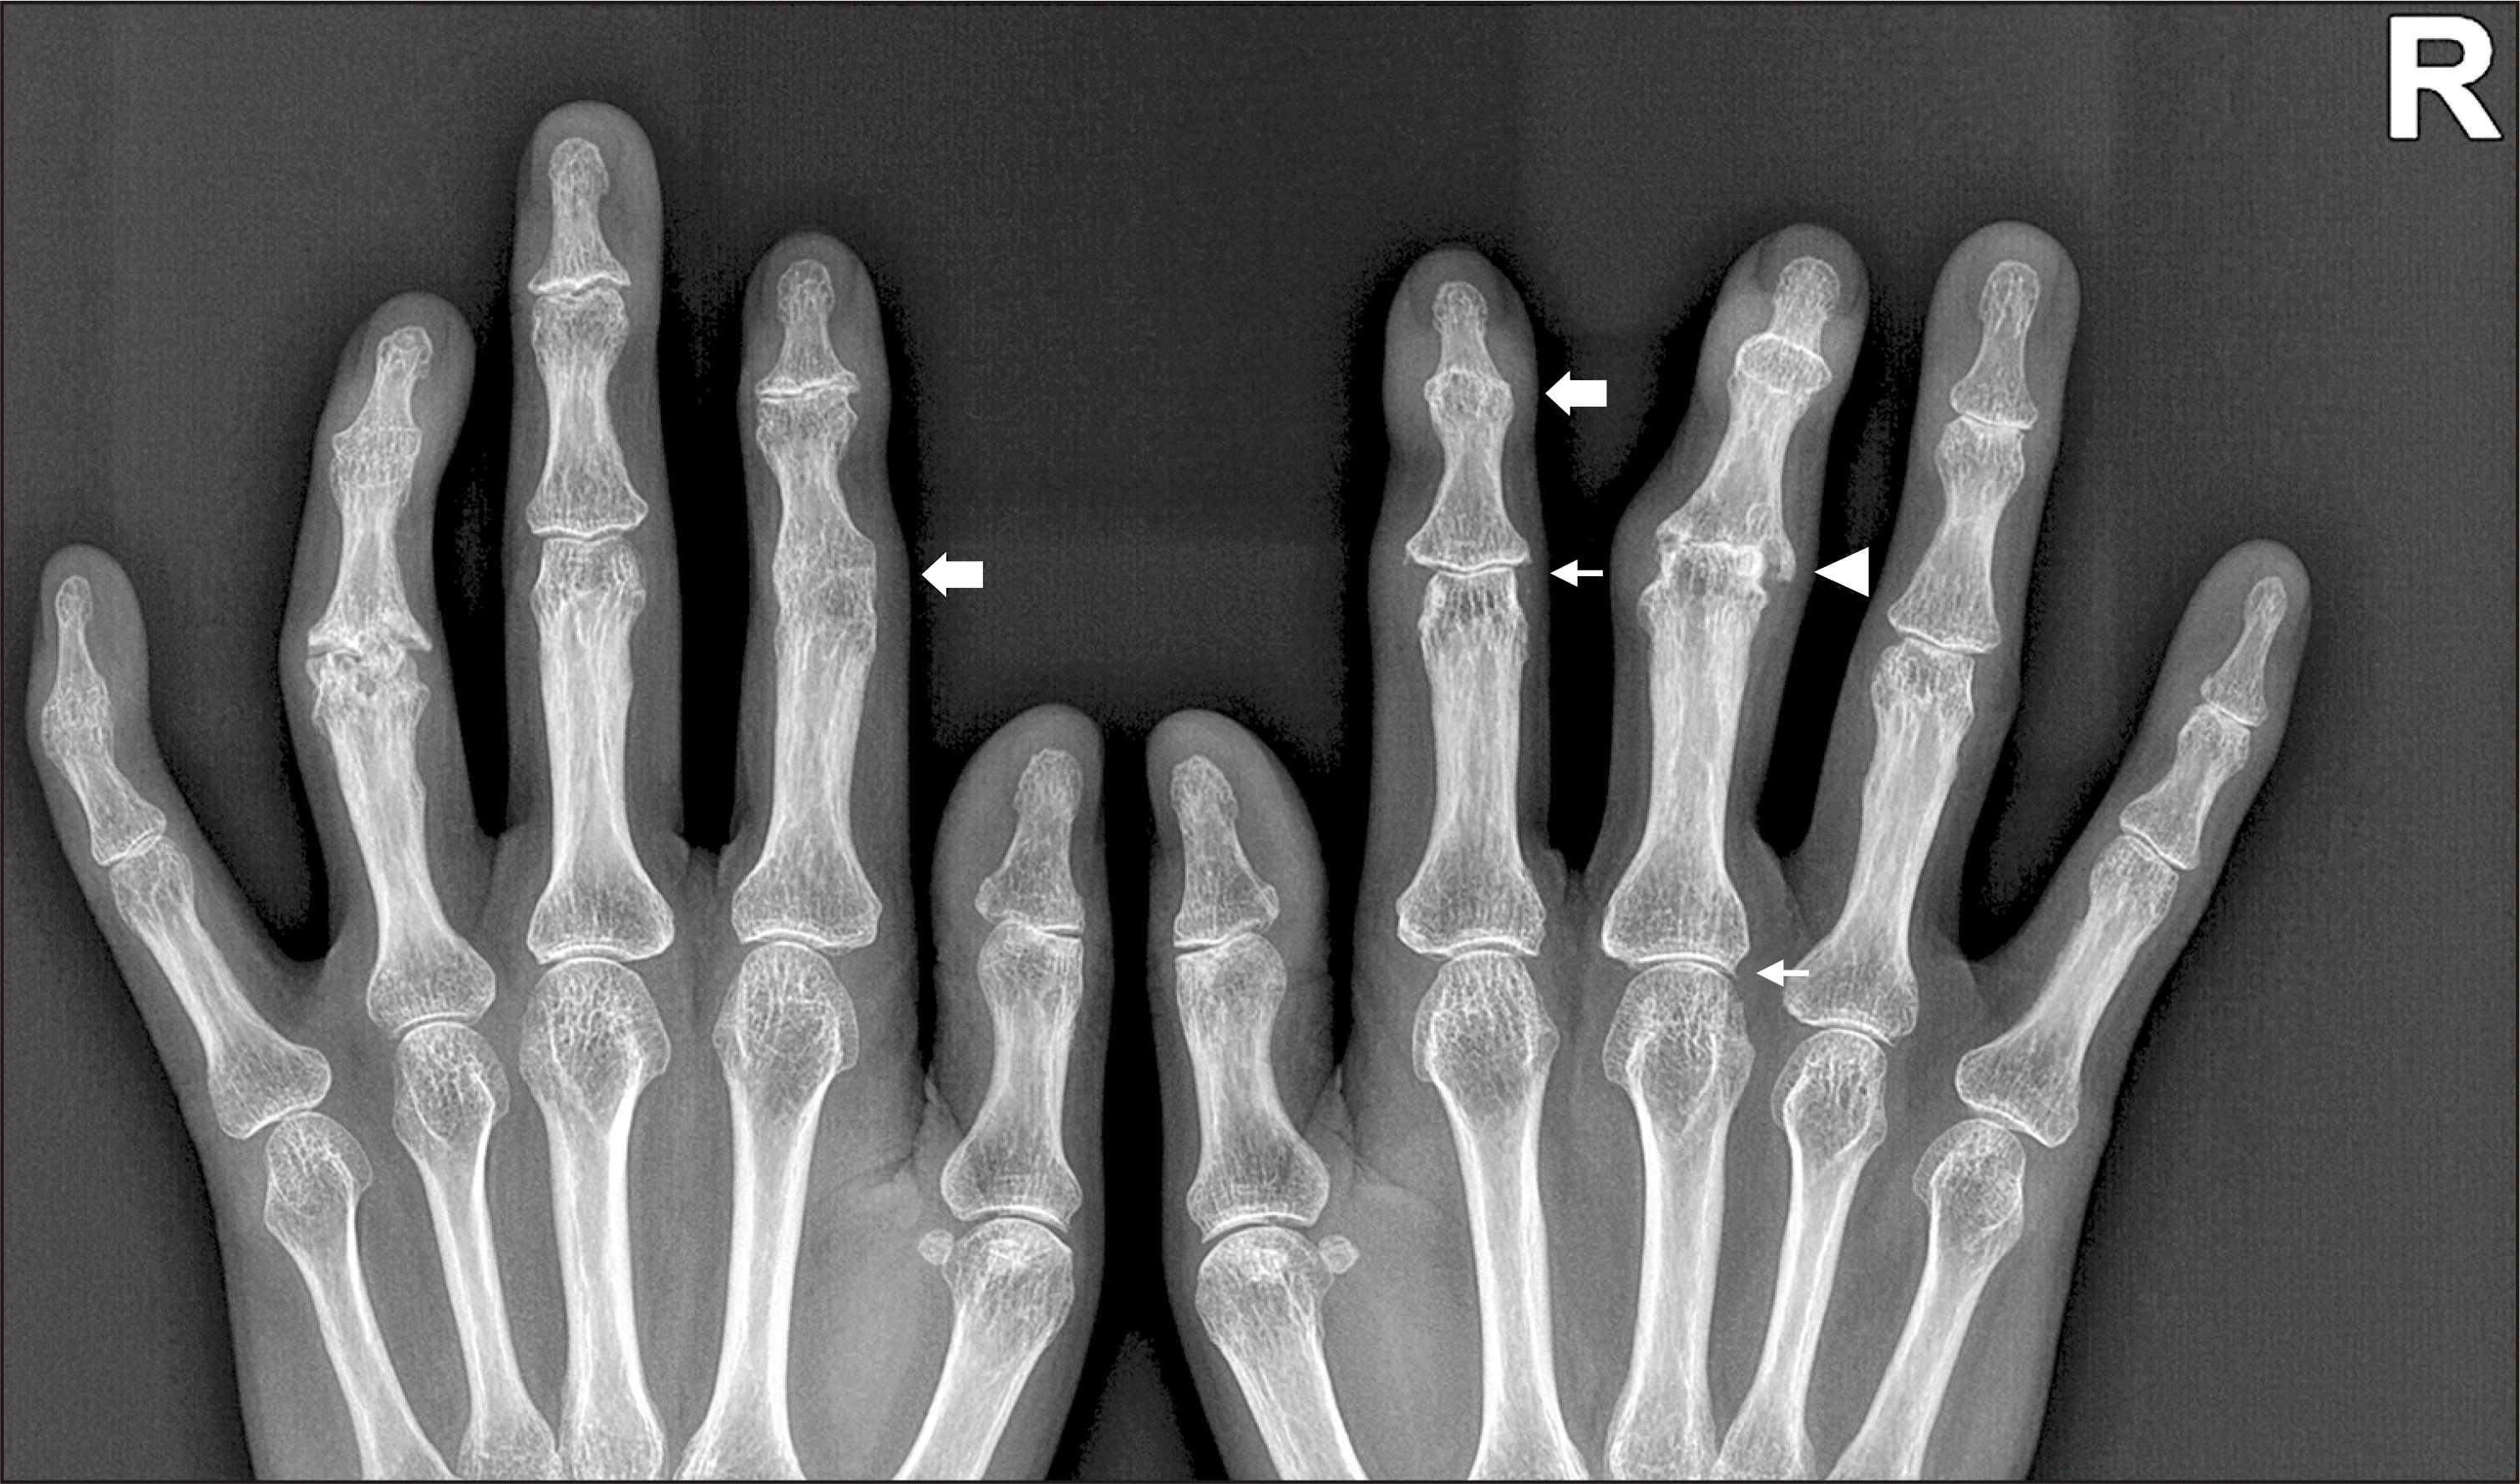

A 50-year-old woman presented with a 4-year history of intermittent swelling and progressive deformities of the hand joints. Serum rheumatoid factor and anti-citrullinated protein antibody tests showed negative results, and the C-reactive protein level was 0.11 mg/dL. Radiograph revealed joint space narrowing, erosions, and subchondral sclerosis involving several proximal interphalangeal (PIP) and distal interphalangeal (DIP) joints of both hands. Of note, we observed periarticular calcifications around the second DIP and PIP, third PIP, and third metacarpophalangeal (MCP) joints on the right and the second PIP joint on the left (thick arrows, Figure 1). Calcific periarthritis and concomitant erosive osteoarthritis were diagnosed and therapy was started with celecoxib. Her hand joint problem progressed and she was not able to flex the right second and third and the left second fingers. Intraarticular glucocorticoid injection was performed at the right second and third PIP and the left second PIP joints and hydroxychloroquine and diacerein were added, which were not effective in improving limitation of motion of the finger joints. She also complained of worsening pain and deformity of the left fourth DIP and PIP joints. Three years later, pain and swelling of the hand joints improved but deformities did not. Follow-up radiograph showed disappearance of all previously observed periarticular calcifications. The right second PIP and third MCP joints showed minimal disease progression (thin arrows, Figure 2). However, we observed ankyloses of the right second DIP and the left second PIP joints (thick arrows, Figure 2) and joint space loss with erosions of the right third PIP joint (arrow head, Figure 2). Additionally, there were ankyloses of the left fourth and fifth DIP joints and severe erosions of the left fourth PIP joint, which had not been affected by calcific periarthritis in the initial radiograph.

Figure 1

Initial radiograph. There are joint space narrowing, erosions, and subchondral sclerosis involving several PIP and DIP joints of both hands. Of note, periarticular calcifications were found around the second DIP and PIP, third PIP, and third MCP joints on the right and the second PIP joint on the left (thick arrows). PIP: proximal interphalangeal, DIP: distal interphalangeal, MCP: metacarpophalangeal.